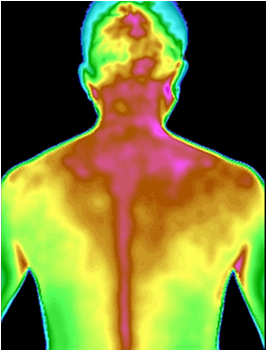

图3 颈肩肌肉劳损红外热成像图